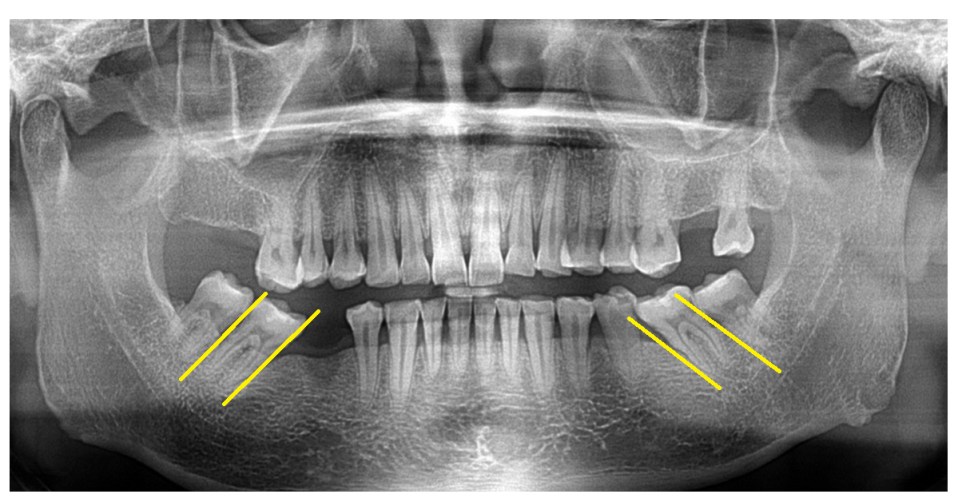

마지막 세 번째 케이스를 볼까요~?

3️⃣위아래 맨 끝 치아가

짝꿍으로 없다

23.08.07

사진 속 환자분을 보겠습니다.

오른쪽 치아도 맨 끝 치아가 위아래로 발치된 상황

왼쪽도 맨 끝 위아래가 없으시네요~

이럴 경우에는 환자분 결정에 맡깁니다.

교과서적으로는 치아가 상실되면

개수대로 심으면 제일 좋겠지만

환자분 상황에 맞춰 심는 게 제일 좋은 치료라 생각합니다.

치아 개수가 부족하다 보니

씹는 힘은 약하겠지만

생활이 안될 정도는 아닙니다.

23.11.04

#27,37 위아래로 치아가 없는 경우에는

양쪽으로 물리는 게 없어서

환자분 결정에 맡깁니다.